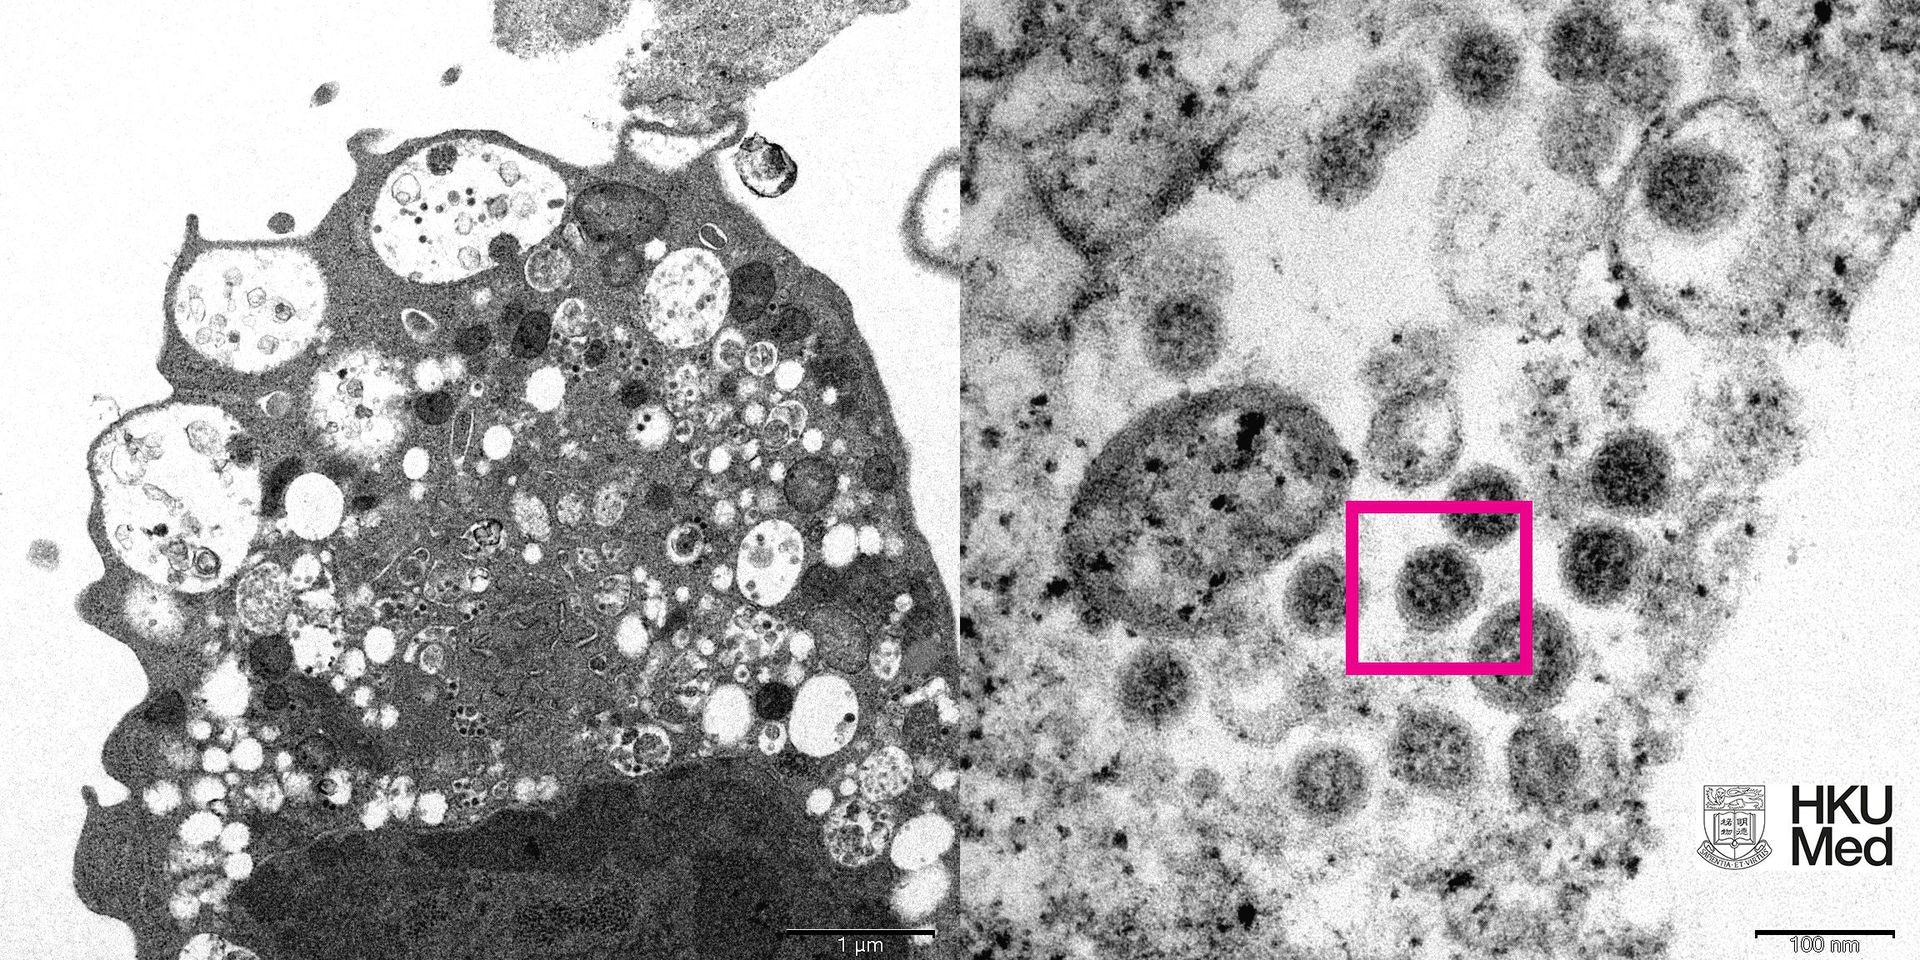

新冠病毒与流感病毒同属于RNA病毒, 病毒基因在人传人过程中不断出现变异,病毒为了自身延续,愈多的传播,进行突变的机会愈高。现时新冠病毒BA.2型至少已有额外二十至三十个基因出现变异,有机会往高传染力、低致死率的方向自然演化。